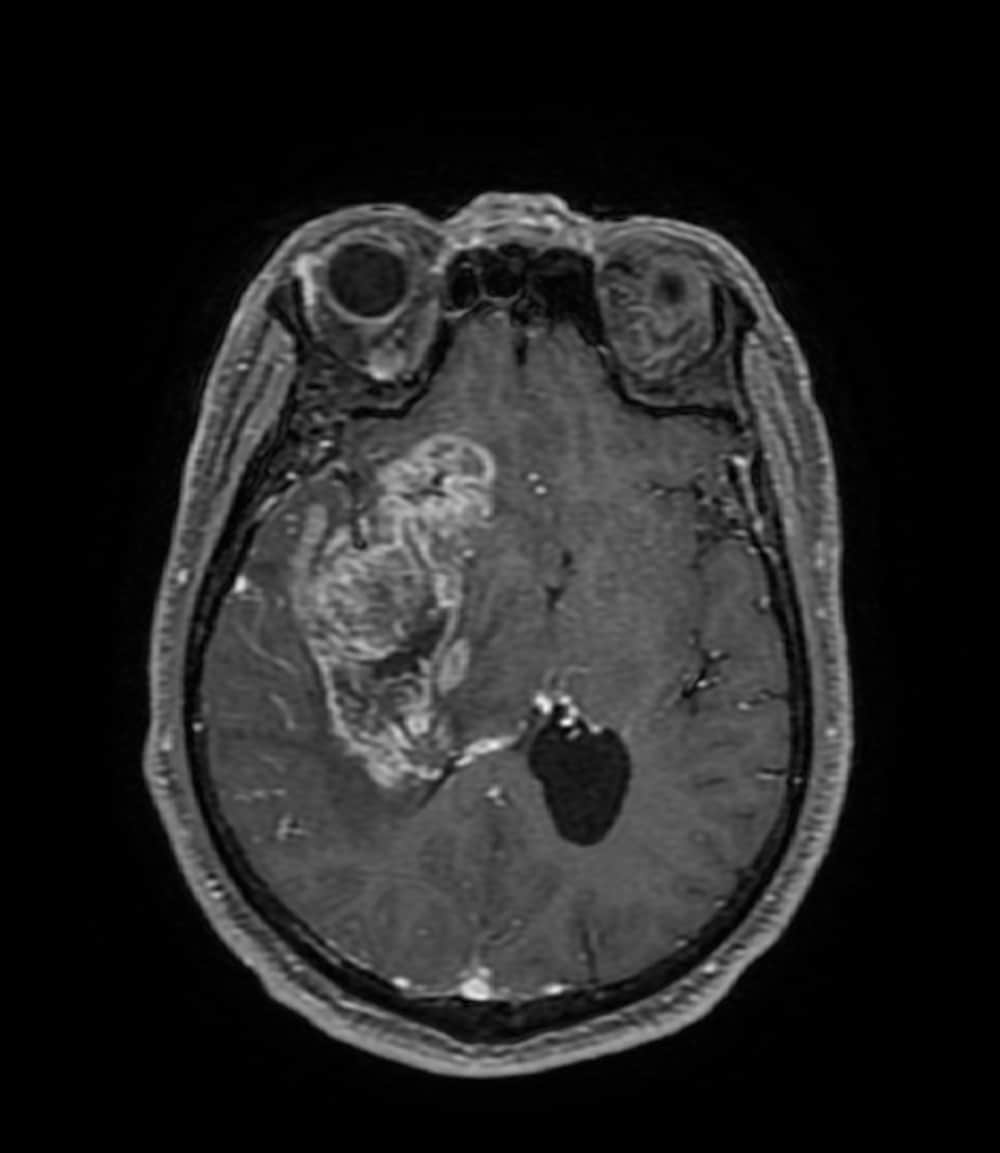

2週間前からの頭痛にて前医を受診し、CTで頭蓋内腫瘤や脳浮腫を認めたため、当院へ救急搬送された。当院で施行された造影MRIでは右側頭葉~前頭葉に約7.5×4cmの辺縁不整な腫瘤を認め、膠芽腫が疑われた。その後手術が施行され膠芽腫の診断に至り、手術後は化学放射線治療が施行された。

当該疾患の診断における造影MRIの役割

受診当日に施行されたCT/MRIにて偶発的に腫瘤が発見された。非造影のCTやT1強調画像、T2強調画像、拡散強調画像などでは腫瘤の存在や輪郭が不明瞭であることも多く、本症例のように造影を行うことで腫瘤の詳細な評価が可能となる。一般的には転移性脳腫瘍や脳膿瘍などが鑑別となり、その他のシーケンスや体幹部の所見、臨床データなどとも併せて診断を行うことが重要である。